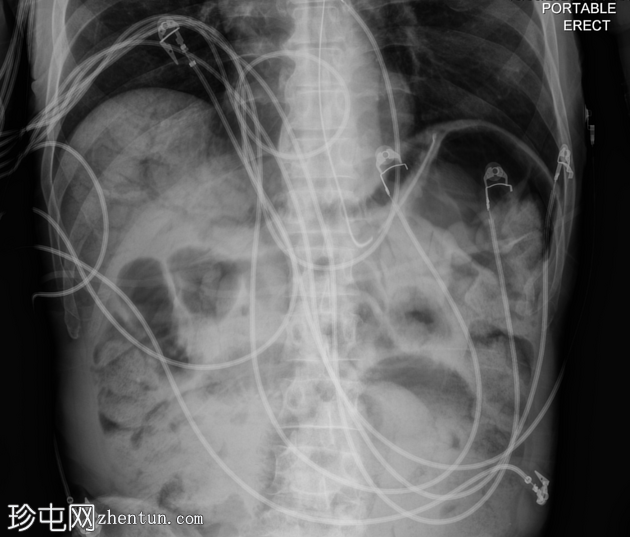

3.png

正位片

4.png